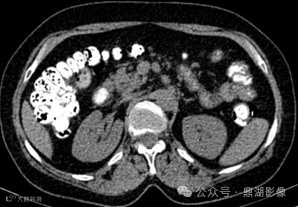

患者,女,55岁,长期腹泻、体重减轻和缺铁性贫血。

CT小肠造影如下

CT增强扫描静脉期

CT小肠造影显示回肠袢轻度扩张,回肠皱襞增多、空肠皱襞减少,并伴有多个肠系膜淋巴结肿大。未发现肠套叠、狭窄或肿块形成等征象。

空回肠皱襞模式反转

空回肠皱襞模式反转(称为回肠空肠化,空肠皱襞减少,回肠皱襞增加)是乳糜泻最特异的征象,文献报道其敏感性和特异性(阳性预测值和阴性预测值)接近100% 。 5cm距离内回肠皱襞数量多于空肠皱襞数量时,则被认为是阳性。

CT和MR小肠造影中,空回肠皱襞模式反转和肠系膜淋巴结肿大是乳糜泻的特征性表现。疾病的严重程度差异极大,从节段性受累到弥漫性小肠受累不等,但最常累及近端空肠。

在CT和MR小肠造影图像上观察到每英寸(=2.54cm)肠段的皱襞少于或等于3个,则认为空肠皱襞密度降低。在重度乳糜泻中,空肠皱襞可能完全消失。在慢性炎症的情况下,回肠皱襞密度可能代偿性增加,定义为每英寸超过5个皱襞,以增加小肠表面积。皱襞数量的增加代表回肠对空肠吸收能力下降的一种适应。